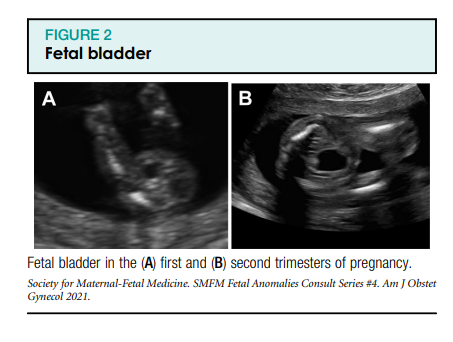

Loote urogenitaalsüsteem hõlmab loote neere, kusejuhasid, põit ning sise- ja välissuguelundeid. Loote urogenitaalsüsteemi standardne ultraheliuuring pärast raseduse esimest trimestrit hõlmab loote neerude ja põie visualiseerimist (joonised 1, A ja B ning 2). Neeruvaagna laienemist tuleks hinnata raseduse teisel ja kolmandal trimestril anteroposterioorse diameetri telgvaates (joonis 1, C). Loote suguelundeid tuleks uurida mitme raseduse ajal, kuna see võib aidata määrata koorionilisust või kui see on meditsiiniliselt näidustatud, näiteks kui patsiendil on X-seotud geneetilise häire oht (joonis 3). Lisaks tuleks mõõta lootevee mahtu (joonis 4), kuna see annab funktsionaalse hinnangu loote neerudele, mis toodavad lootevett pärast 16–17 rasedusnädalat. Neerupatoloogia võib seetõttu põhjustada nii lootevee mahu suurenemist kui ka vähenemist.